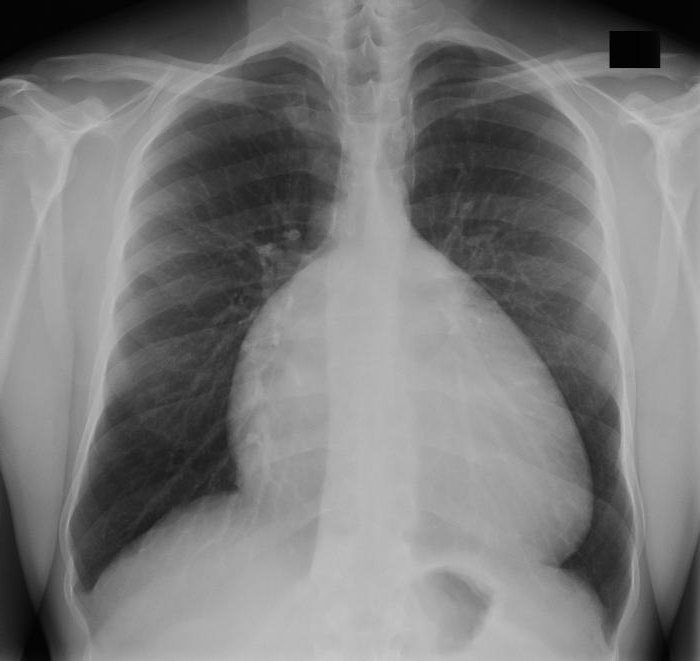

На рентгенографии визуализируется расширенная сердечная тень, это происходит из-за значительного увеличения правого предсердия. Сосудистый рисунок легких обычно бледен. Сердце часто принимает форму шара.

- Рентгенография грудной клетки. Помогает выявить кардиомегалию различной степени , характерную именно для аномалии Эбштейна. которая возникает из-за увеличенного правого предсердия. При этом левая часть сердца остается в норме. На снимке сердце имеет шаровидную форму, легочные поля довольно прозрачны.

- Рентгенография – правое предсердие придает контуру сердца форму шара, легочные поля прозрачные.

При рентгенологическом исследовании

выявляют увеличение правого предсердия и маленький правый желудочек.